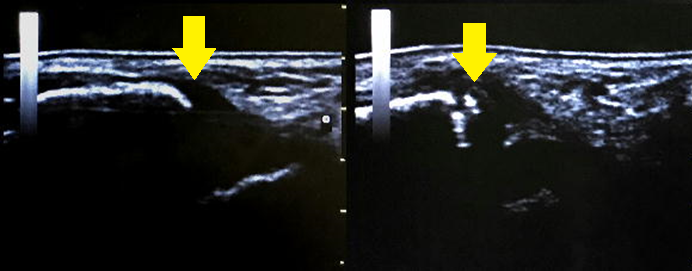

※画像:左が健側、右が患側です。

【症例4 ☆重要症例 腓骨遠位端部裂離骨折(足関節捻挫ではない!)】

小学2年生。遊具から飛び降りた際に着地を失敗して足首をひねり負傷し、来院。

10歳未満の怪我は捻挫と思っていても実際は骨折をしていることがとても多い。